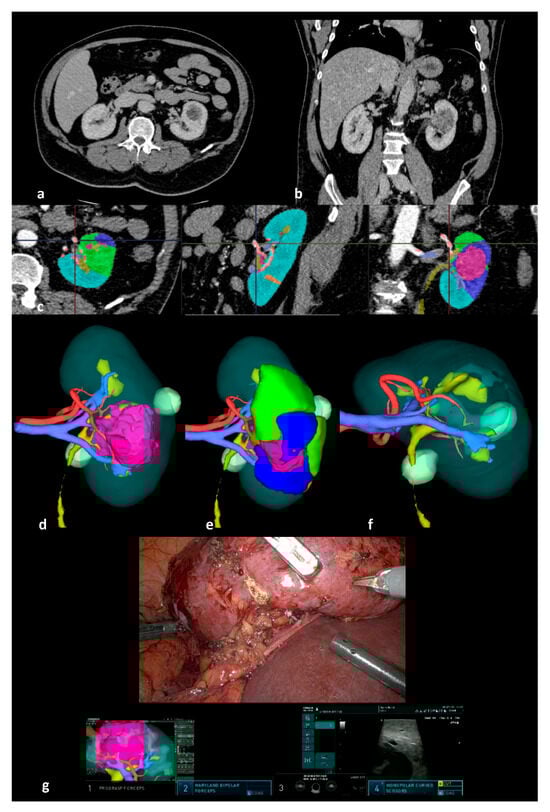

Assessing Oncologic and Functional Outcomes of 3D Image-Guided Robotic-Assisted Partial Nephrectomy (3D-IGRAPN): A Prospective Study (UroCCR-186)

2. Materials and Methods